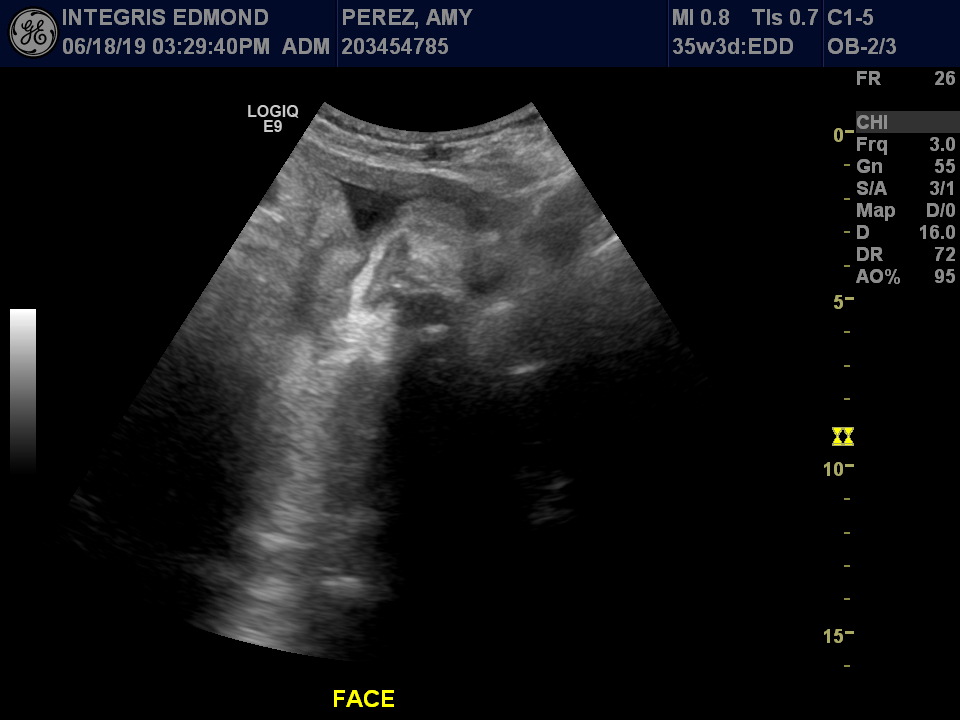

FINAL SONOGRAM

Everything checked out good. She is between 5-6 lbs and they said she is only two days off her due date of July 20th + or - a week. Dr. Sparks said she wouldn’t let Amy go past 40 weeks though, so the countdown officially begins.